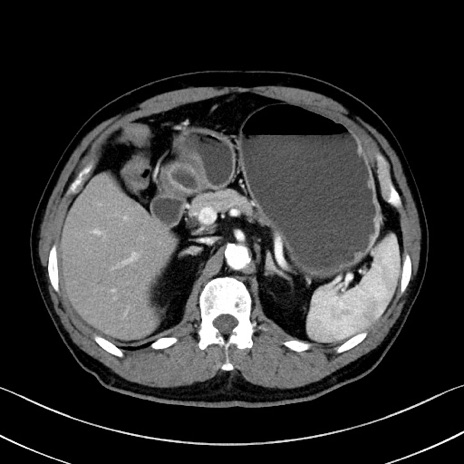

症例35(横断像)

【症例】70歳代 男性

【主訴】腹部膨満、嘔吐

【現病歴】昨日より腹部膨満感出現。本日増悪し、仙痛出現。嘔吐あり、受診。

【既往歴】糖尿病、胆摘後

【身体所見】BP 149/80mmHg、HR 74/min、BT 35.9℃、腹部:膨満、軟、圧痛なし。腸雑音減弱あり。上腹部正中切開瘢痕あり。

【データ】WBC 13500、CRP 1.72